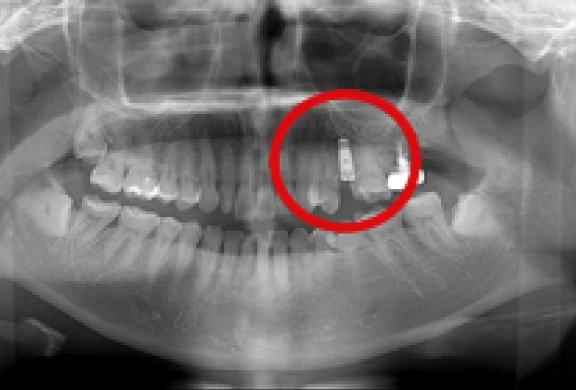

歯間部のインプラント

(2本、上部構造の装着)

-

上顎のインプラント